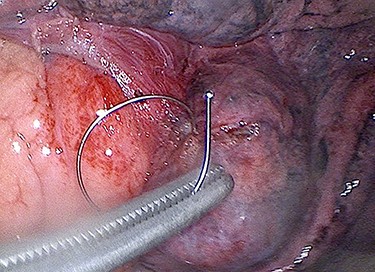

A 61-year-old man presented with 2 weeks of pleuritic chest pain and small-volume haemoptysis. He had undergone left lower lobe endobronchial coil insertion 6 months prior. Computed tomography scanning revealed perforation of the lung parenchyma and mediastinal pleura by an endobronchial coil (Fig. 1), with its tip penetrating the pericardium and abutting myocardium. Trans-thoracic echocardiography demonstrated a sub-centimetre pericardial collection along the inferior cardiac wall without cardiac tamponade.

Via a single 4 cm incision for video-assisted thoracoscopic surgery (VATS) (Fig. 2), the embedded endobronchial coil was carefully manipulated out of the superficial lung parenchyma and epicardial fat, and wedge resection of the damaged lung performed. There was no penetrating cardiac injury. The patient made an uneventful recovery.